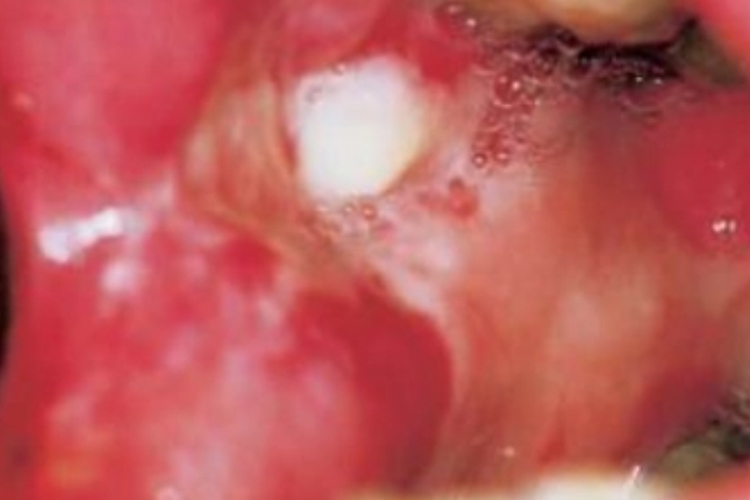

二期梅毒:二期梅毒在口腔的常见表现为咽部、扁桃体的炎症。表现为黏膜斑,呈浅在圆形或椭圆形糜烂表面,有光滑的灰白色渗出膜,形似疱,周围有斑片状充血发红区。